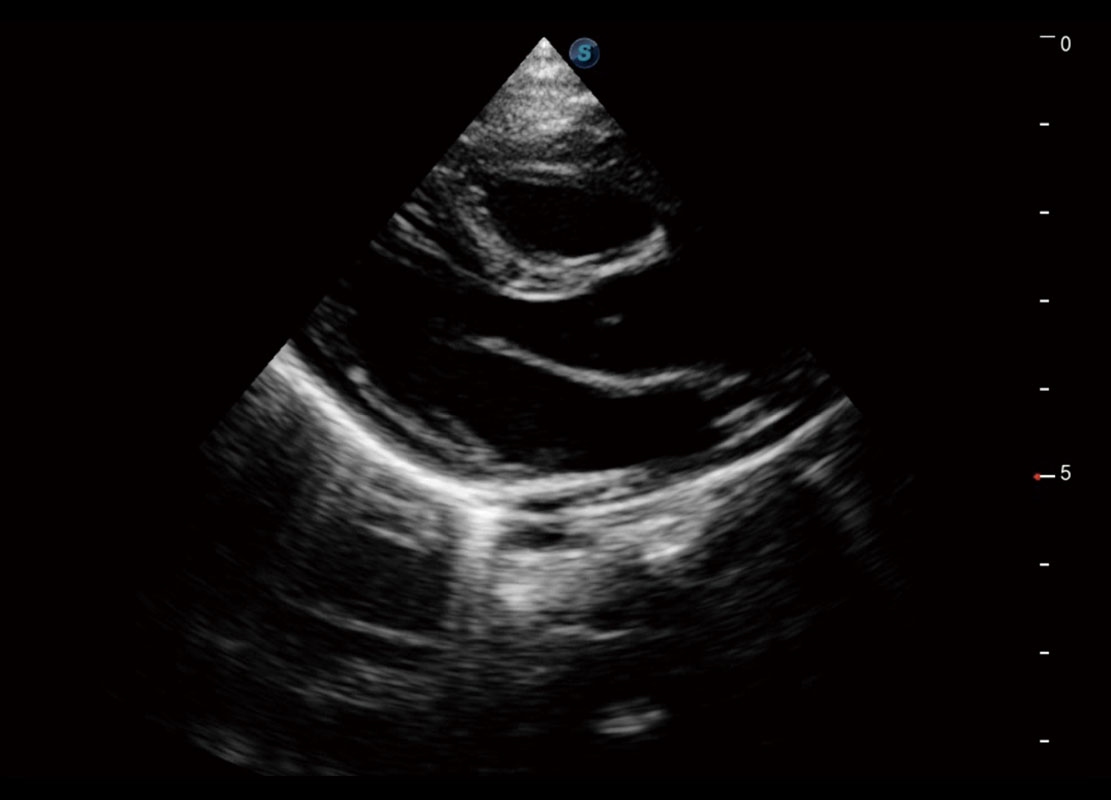

乳腺超声 / 新生儿

• 新生儿肝血管癌

• 新生儿脊髓圆锥

• 新生儿心脏